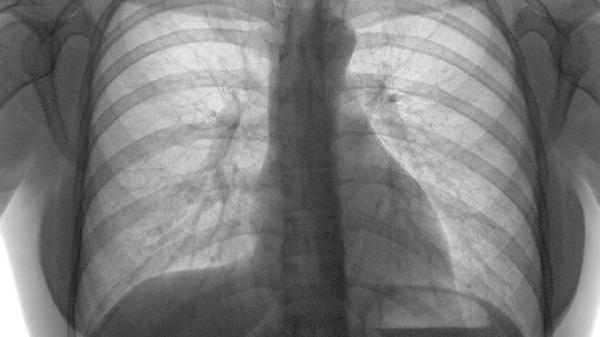

肝炎可能与病毒感染、酒精损伤等因素有关,通常表现为肝区隐痛、乏力、黄疸等症状。需通过肝功能检查明确诊断,遵医嘱使用复方甘草酸苷片、水飞蓟宾胶囊、恩替卡韦分散片等药物。患者应戒酒,避免使用肝毒性药物,保证充足休息。